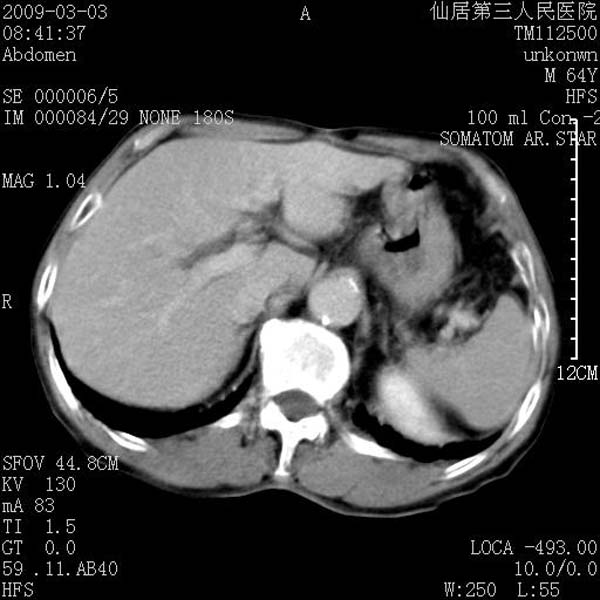

标题: CT18469:男性,64y,体检B超示肝脏低回声肿块,有胃溃疡手术 [打印本页]

患者,男性,64y,体检b超示肝脏低回声肿块,有胃溃疡手术史。

考虑----胃肠道间质瘤可能性大

从平扫及增强的特点来看,支持肝脏腺瘤并出血。

考虑胃间质瘤可能性大。

胃肠道间质瘤!

ct值呢?感觉没强化,象囊性。

考虑肝静脉韧带裂区良性占位性病变(囊肿?)。

考虑肝囊肿并出血可能性大.

考虑高密度囊肿可能性大